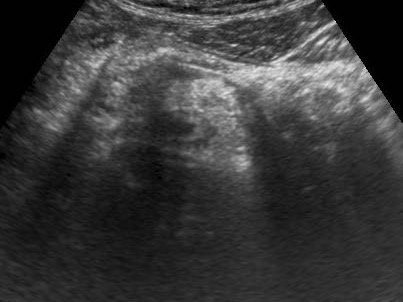

Trong 6-12 giờ đầu, lòng ruột thừa giãn rộng rõ rệt với thành mỏng và chưa có hiện tượng viêm mô mỡ xung quanh.

Bệnh nhân này nhập viện với cơn đau quanh rốn dữ dội, cấp tính kéo dài 4 giờ và không có đau khu trú tại vị trí ruột thừa giãn (giai đoạn đau tạng).

Lưu ý hiện tượng phồng của ruột thừa căng vào thành bụng (đầu mũi tên) trong khi ép.

Những ruột thừa này dễ bị bỏ sót trong quá trình khám siêu âm, do không có đau khu trú và không có hiện tượng viêm mô mỡ.

Hơn nữa, những bệnh nhân này thường được cho về nhà mà không được siêu âm hay CT, vì các triệu chứng đau tạng của họ được diễn giải và điều trị như “vấn đề dạ dày hoặc túi mật”.

Mô mỡ viêm

Mô mỡ đầu tiên bị ảnh hưởng trong viêm ruột thừa là mạc treo ruột thừa (meso-appendix).

Mạc treo ruột thừa bình thường có thể được nhận diện khi được bao quanh bởi một ít dịch trong phúc mạc như ở bệnh nhân này, và có đặc điểm tăng âm vừa phải, mềm mại và dễ ép xẹp.

Khoảng 4-6 giờ sau khi khởi phát triệu chứng, tình trạng viêm bắt đầu ảnh hưởng đến mạc treo ruột thừa, khiến nó to hơn, tăng âm hơn và không thể ép xẹp (đầu mũi tên).

Sự sản xuất fibrin tiếp theo trên bề mặt thanh mạc gây ra viêm phúc mạc khu trú, dẫn đến hiện tượng chuyển đau điển hình từ vùng quanh rốn hoặc thượng vị sang hố chậu phải.

Điều thú vị là trong giai đoạn sớm của viêm mô mỡ, siêu âm nhạy hơn CT.